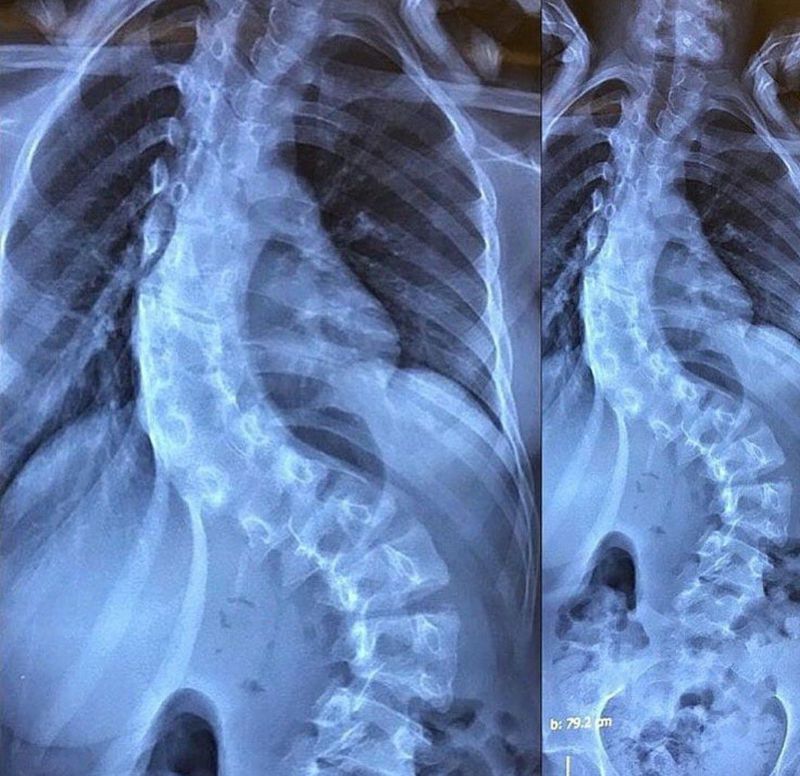

What's your diagnosis?

Chronic Scoliosis

Severe scoliosis

Its just me or the pelvis is very 'up' compared where is supposed to be